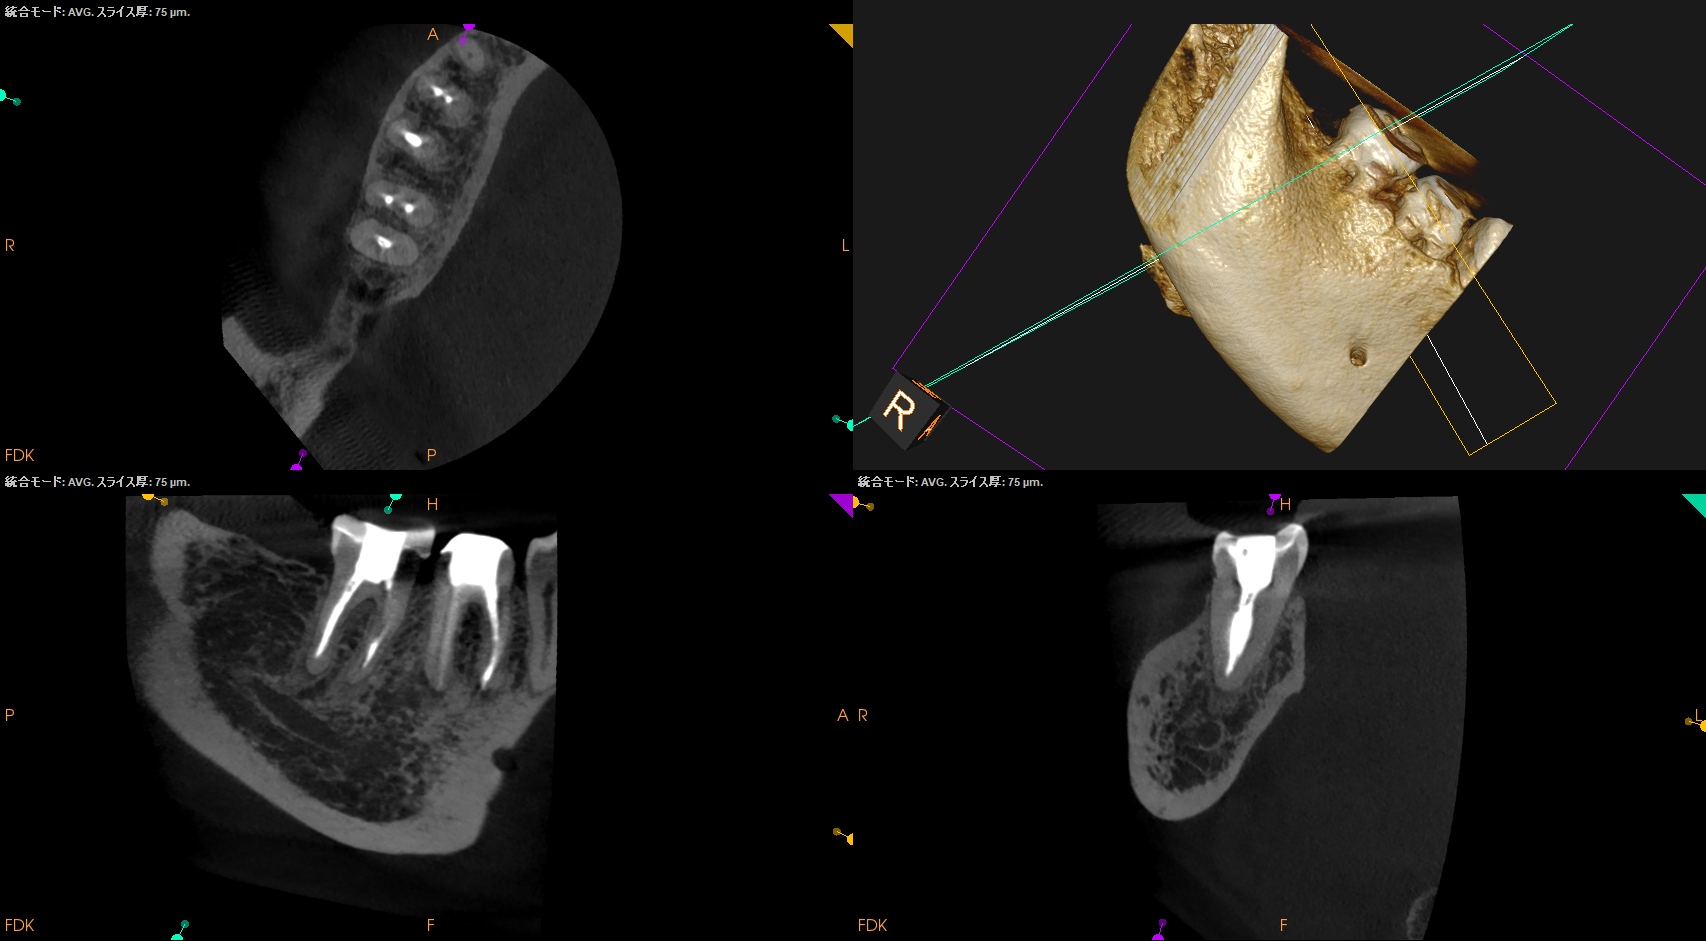

#31 RCT+Core build up(2025.9.12)

MLをメイン根管にし、MBがそこに合流する形式とした。

MLはMAFは当初は#40.04であったが#60.02に変更した。

炎症がまだ残存していると考え、MAFを#60.02まで上げた。

根充してPA, CBCTを撮影した。

MB

ML

D

問題はないだろう。